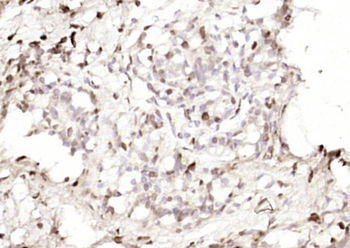

100 μl, 50 μl, 25 μl - Rad51 Recombinant Rabbit Monoclonal Antibody [orb608069]Featured

IF, IHC-Fr, IHC-P, WB

Human, Mouse, Rat

Mouse, Rat

Rabbit

Recombinant

Unconjugated

50 μl, 100 μl - KLF4 Recombinant Rabbit Monoclonal Antibody [orb608075]Featured